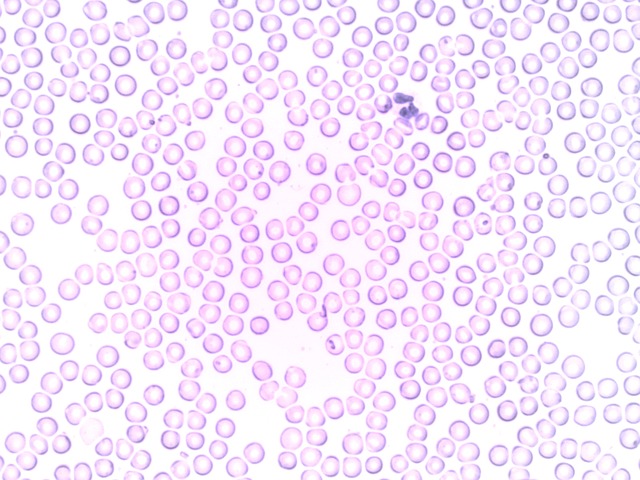

Beim Betrachten der beiden Aufnahmen sehen Sie den grundsätzlichen Unterschied. Um beim Beispiel „Himmel“ zu bleiben: Selbst wenn der Himmel wolkenlos ist, sieht man mit dem bloßen Auge nur die Sonne, vielleicht noch den Mond. Die umliegenden Sterne bleiben dem Auge verborgen – eine Metapher, die das grundsätzliche Prinzip der Dunkelfeldmikrokopie auch für Laien sehr anschaulich erklärt.